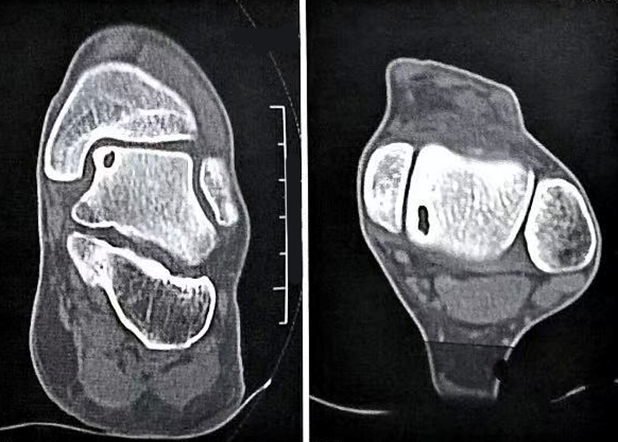

图3:X光片示距骨软骨损伤(红色箭头)

图4:CT示距骨软骨损伤